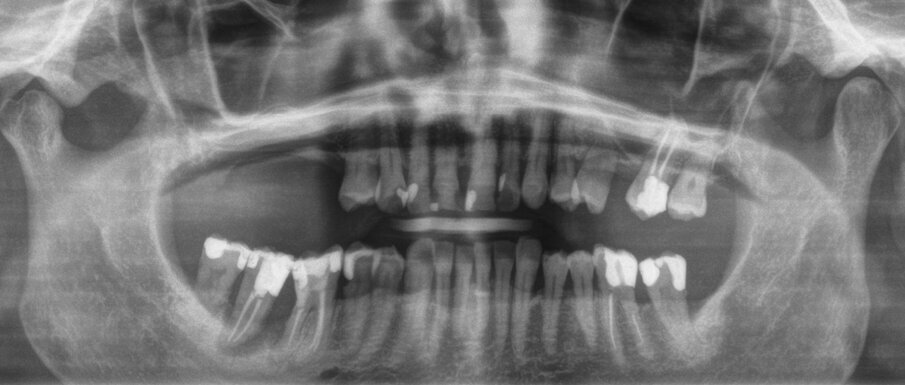

Una paziente di 62 anni, ASA I, non fumatrice e non diabetica, con malattia parodontale precedentemente trattata, si è presentata per una riabilitazione implanto-protesica del mascellare superiore (Fig. 1). L’analisi radiografica, eseguita tramite ortopantomografia (OPT) e tomografia computerizzata cone-beam (CBCT), ha rilevato la presenza di un difetto osseo verticale nel primo sestante, dovuto alla completa perdita del processo alveolare (Figg. 2, 3). Dopo aver discusso con la paziente le possibilità di trattamento, è stato accettato il trattamento proposto come prima scelta, ovvero la ricostruzione ossea del processo alveolare e la successiva riabilitazione mediante corone singole su impianti.

Il piano di trattamento è stato sviluppato utilizzando un flusso di lavoro completamente digitale. Pertanto, i files .DICOM ottenuti dalla CBCT pre-operatoria sono stati utilizzati per generare una ricostruzione 3D del mascellare, che ha permesso di eseguire la progettazione virtuale del volume osseo “ideale” per l’inserimento di 3 impianti in sede #15, #16, e #17. (Figg. 4, 5). Successivamente, è stata creata virtualmente la griglia customizzata corrispondente al volume aumentato nel mascellare della paziente (Fig. 6). Il giorno della chirurgia ricostruttiva (T0), è stata eseguita una profilassi antibiotica (2 g di amoxicillina con acido clavulanico e 500 mg di metronidazolo), una profilassi antinfiammatoria (20 mg di piroxicam), una sedazione cosciente x os (2 ml di delorazepam e 2 ml di diazepam), e disinfezione del cavo orale (risciacquo orale con povidone-iodio per un minuto, perossido di idrogeno per due minuti, e collutorio alla clorexidina 0,2% per tre minuti), e un’anestesia locale mediante articaina 4% contenente adrenalina 1:100.00018. L’esame obiettivo mostra la gravità del difetto osseo che determina un evidente difetto di volume sia in senso orizzontale che in senso verticale (Figg. 7, 8).